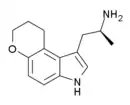

| CP-132,484 | artificial | 1-methyl-4,5-(OCH2CH2CH2) | H | H | 1-(2-aminoethyl)-3-methyl-8,9-dihydropyrano(3,2-e)indole | 143508-76-3 |

| 4,5-DHP-DMT | artificial | 4,5-(OCH2CH2CH2) | CH3 | CH3 | 1-(2-dimethylaminoethyl)-8,9-dihydropyrano[3,2-e]indole | 135360-97-3 |